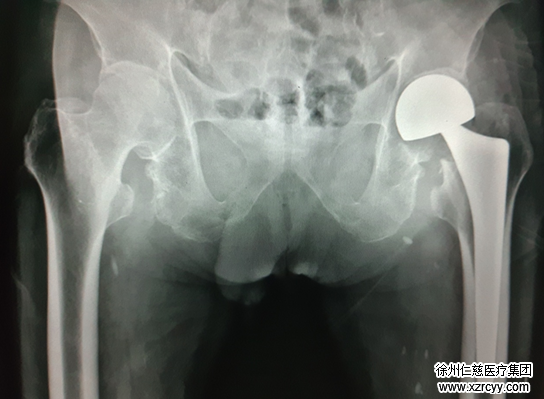

术后片